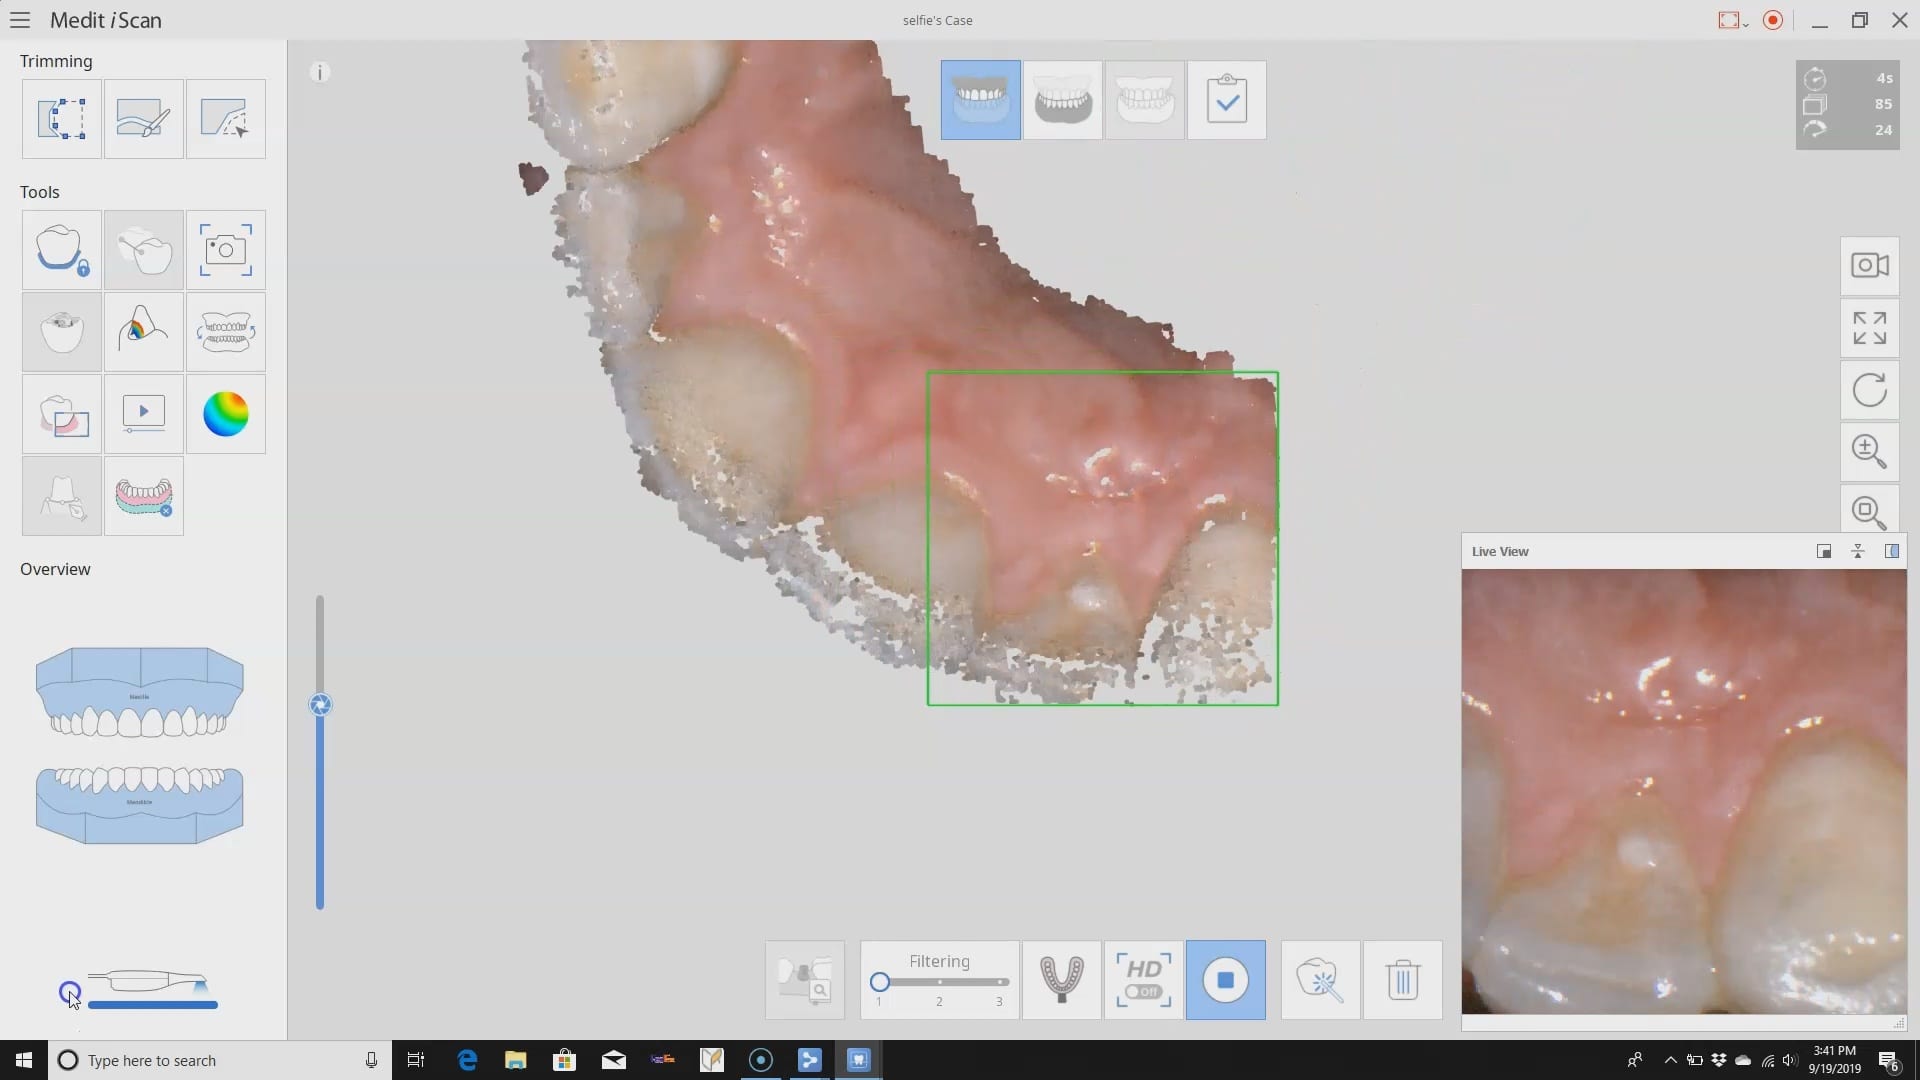

- This is a sample video of a full mouth rehabilitation you will learn how to manage by late morning of Day 1

Full arch scans for aligners and other appliance can be tricky with a lot of intra-oral scanners. With some sound principles and easy tutorials you can image a full arch in very little time. The reliability map, unique to the Medit i500 helps you stay on track and avoid model distortion and inaccuracies